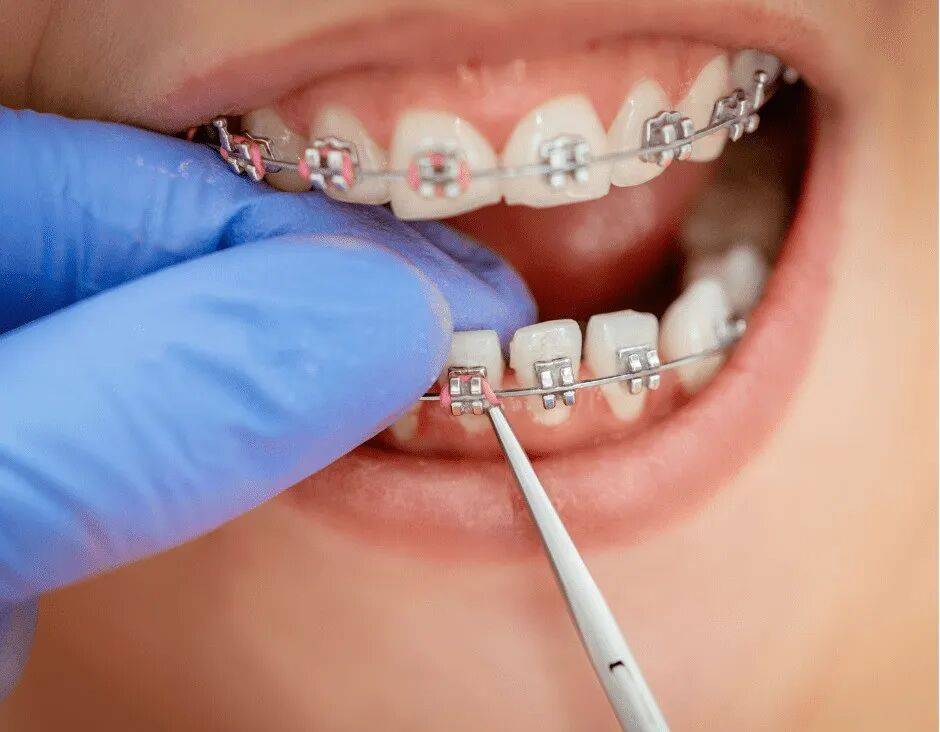

牙科应用中的复合材料

复合材料已成为各种牙科手术中不可或缺的一部分,既提高了牙科手术的功能性,又提高了美观性。它们用于复合树脂填充物、牙冠和牙桥、牙套、牙贴面和牙科粘合剂。强度、美观性和生物相容性的结合使牙科解决方案更有效、更持久,彻底改变了口腔保健方法。

复合材料的进步改善了各种过程,例如牙种植体中的骨整合;其中种植体与颌骨整合,作为牙齿替换的长期解决方案。在正畸学中,复合材料使更不显眼、更舒适的牙套和矫正器的发展成为可能,大大改善了患者的体验。此外,由碳纤维增强塑料 (CFRP) 等复合材料制成的仪器可以与 X 射线机器配合使用,而金属材料会干扰 X 射线机器。

生物相容性和美学效益

先进复合材料的生物相容性是一大优势,因为它可以最大限度地降低过敏反应和身体排斥植入物的风险。从美学角度来看,这些材料可以与牙齿的自然颜色相匹配,为牙齿修复提供无缝自然的外观。生物相容性和美学吸引力的结合显著提高了患者对牙科治疗的满意度和效果。